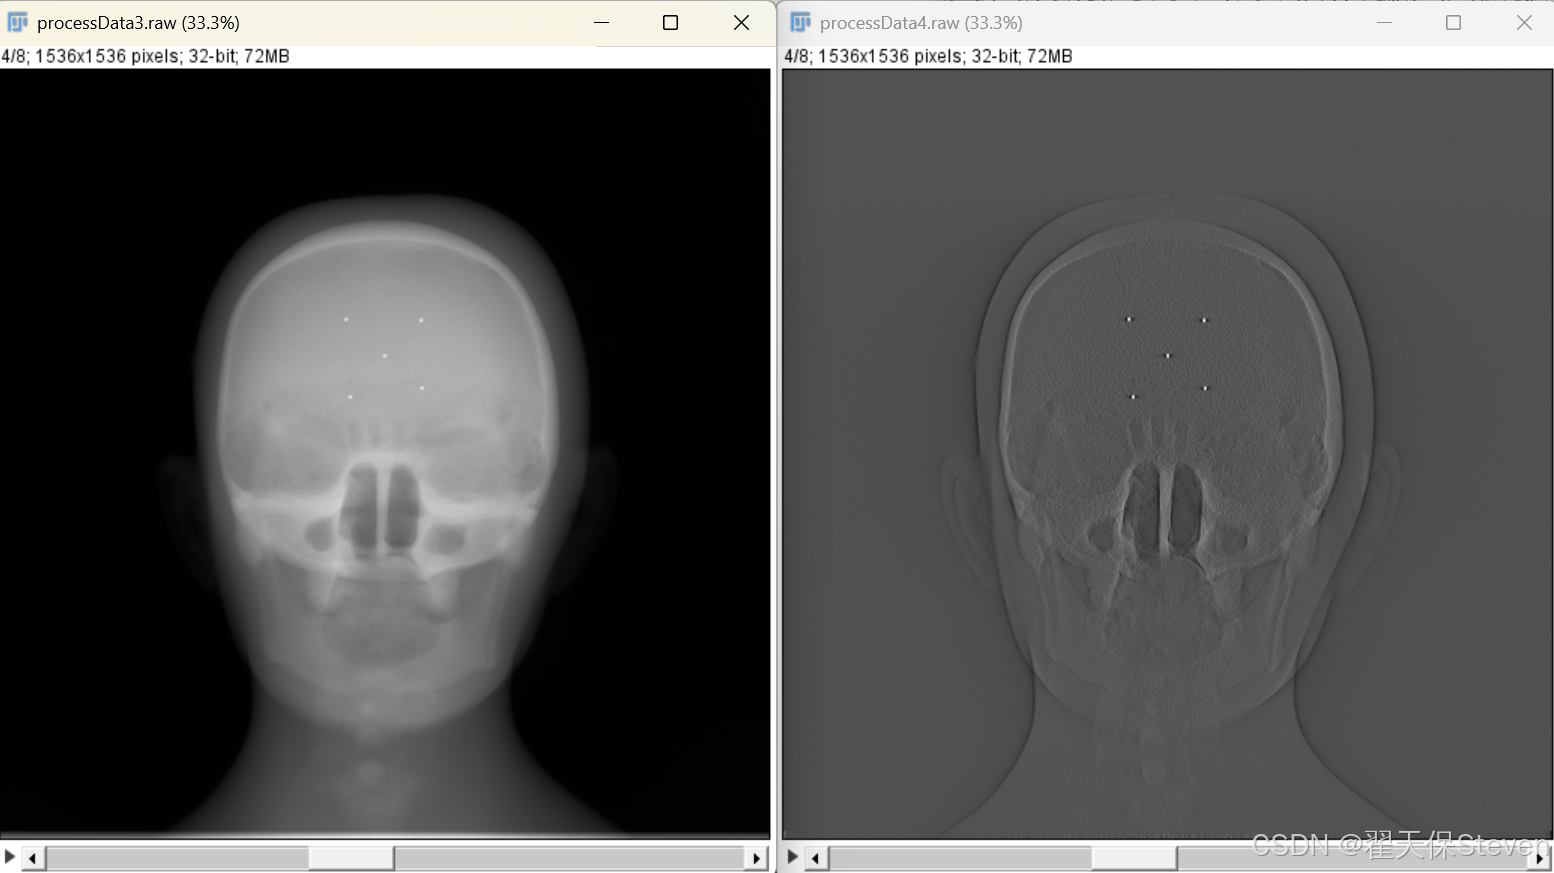

3.4 斜坡滤波

投影数据经过加权后,仍包含大量低频噪声与模糊信息,需通过滤波处理增强边缘细节,提取与物体密度突变相关的高频信息。FDK算法采用斜坡(Ramp)滤波函数,其核心是在频域对投影数据进行加权,放大高频成分。

其中ω为频率变量。由于计算机处理的是离散数据,实际实现中需将频域滤波转换为空域卷积运算,滤波后的投影数据为:

其中表示卷积运算,g(a)为斜坡滤波函数的空域形式。为避免滤波过程中产生的高频噪声放大,实际应用中常将斜坡滤波与窗函数(如Shepp-Logan窗)结合,平衡边缘增强与噪声抑制效果。

滤波过程的核心作用是补偿投影数据在采集过程中的"积分模糊",还原物体密度的突变边界,为后续精确反投影提供清晰的投影信息。